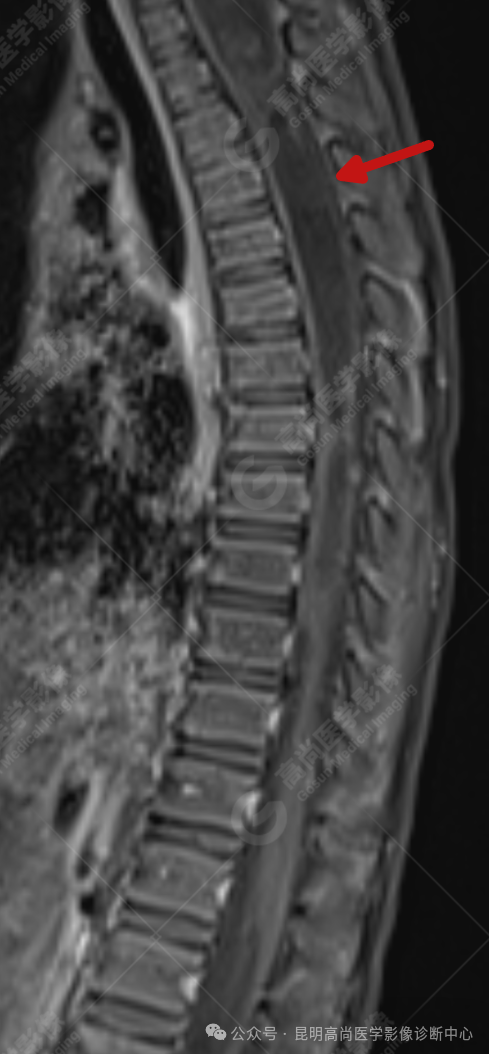

患者女,5 岁,出生时发现颈部包块,大小 3 cm×3 cm,5 年来无变化,拟行手术治疗,要求增强核磁协诊,否认体内金属物,无过敏史。

影像表现

颈 3-5 层面颈后部软组织不规则片状异常信号影,脊膜膨出可能;颈 3、4 棘突局部显示不清;颈胸髓内(约颈 3-胸 9 椎体水平)异常信号影,考虑囊肿并局部颈髓空洞可能,肿瘤或其他待排;请结合临床及相关检查。